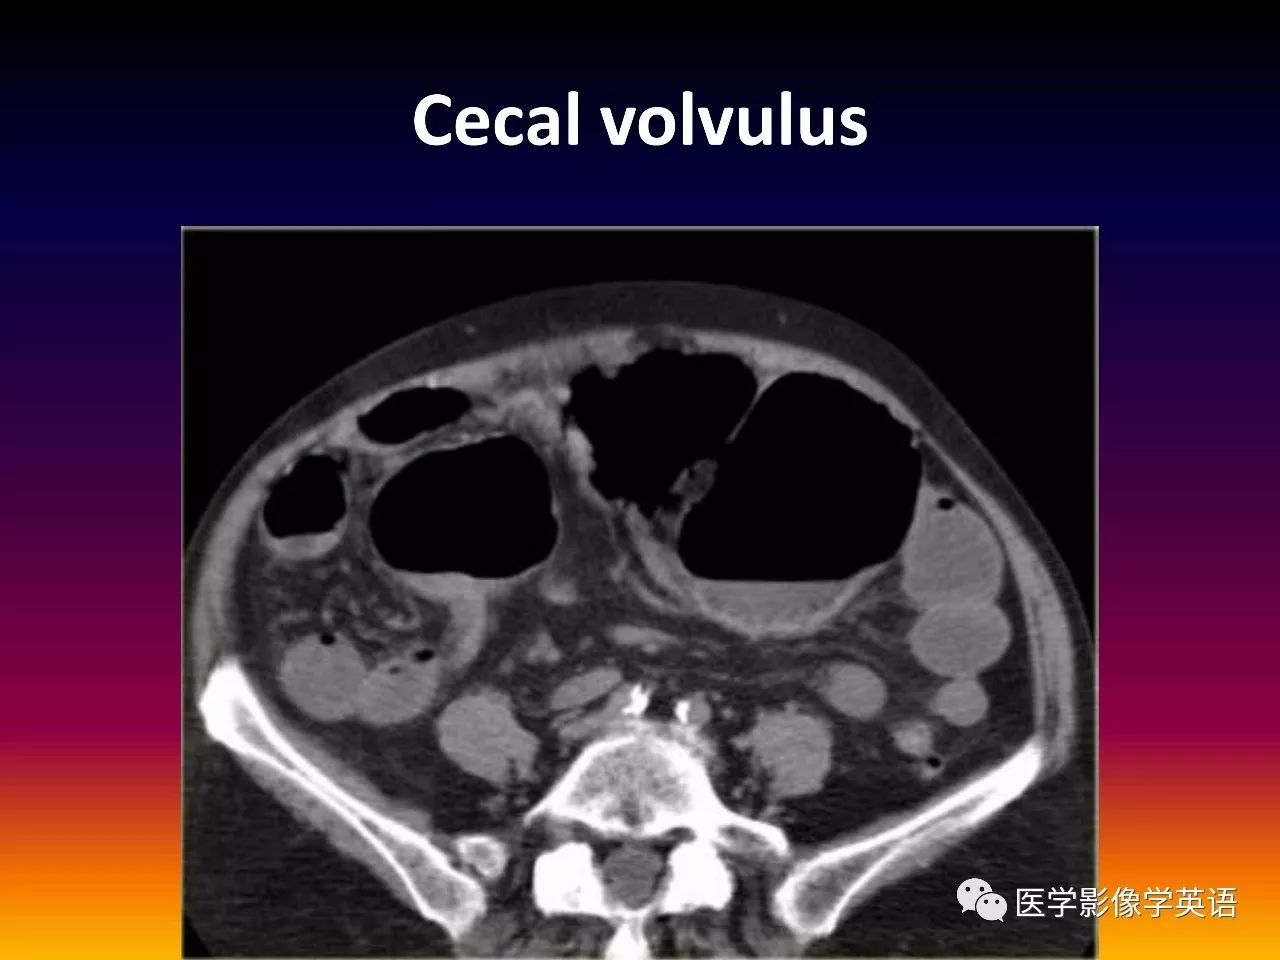

93. Cecal volvulus

94. Cecal volvulus

95. Cecal volvulus

96. Cecal volvulus

97. Cecal volvulus

98. Cecal volvulus

99. Cecal volvulus

100. Cecal volvulus